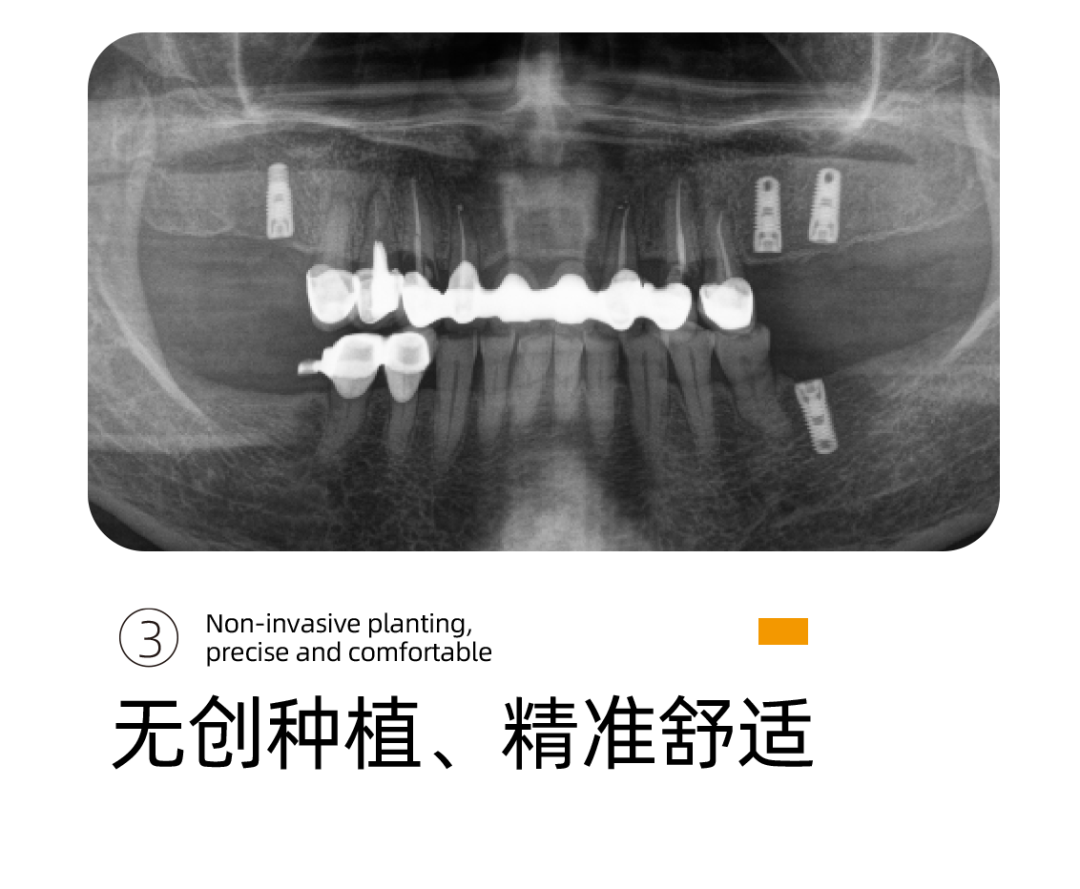

下牙种植完成后,阿姨的感受很好,基本没有疼痛感只有稍微的不适应,重新找回的牙齿让阿姨多了很多生活的幸福。

UNIC种植体系完美打造专属于患者的“私人订制”完整种植闭环,数字化微创种植结合数字化椅旁修复方式,真正实现当天种植、当天戴牙,其中最大的优点就是可以在术中减少患者的痛苦,提高患者的舒适感。

李雪松院长通过德国数字化口腔扫描设备获取的口内数据完全拟合设计,告别传统种植手术中通过大翻瓣暴露手术区域以及解剖结构的方式,缩短就诊以及手术时间,大幅度降低患者术中的疼痛感。

当天,阿姨就带上了牙 ,恢复了咀嚼的功能。

精准、高效、微创性瞬间提升,伤口更小,出血更少,恢复的更快更好。